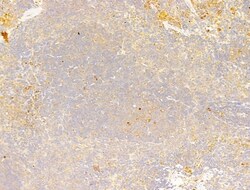

| Immunocytochemistry, Immunohistochemistry (Paraffin), Western Blot | |